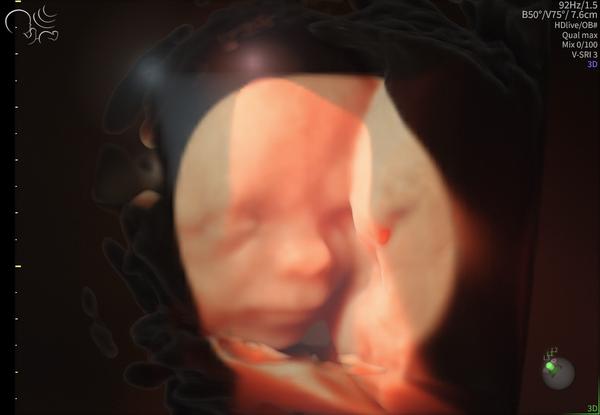

Dámy, aj my sa hlásime, aj keď sem už málo chodím. Včera sme spolu s mojou láskou prekročili polovicu cesty... Držíme všetky palce a posielame babätkovské bacily.

@bambulka711 bozeeee aký krásny 😍

@zanzilady veru, dokonalý je. Škoda, že video sa nedá nahrať, aj by zakýval skupinke 🥰

@bambulka711 to je už take naozajstne keď to vidíš že ma každú časť tela 🥹a ty sa ako cítiš ?

@zanzilady ja super, okrem funenia, keď idem do schodov, ani neviem. Ale už krásne cítim pohyby a kopkanie. Užívam si to veľmi. A veru skutočné, včera sa mi podarilo kúpiť vajíčko aj so základňou za super cenu, tak už prvú vec pre neho mám aj doma. Chodím pozerať kočíky, riešim výbavičku, naši sa neskutočne tešia. Zvládneme aj bez ocka. A hlavne mi v pondelok doktor Grochal povedal, že ma nemá ani čím postrašiť, že je dokonalý 🥰

@bambulka711 jeeeej aký je krásny 🥹🥰🥰 v ktorom si tt my sme už pomaličky na konci 36tt 🩷🌸